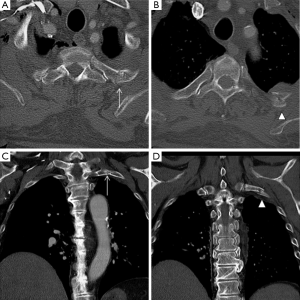

Sternal or clavicular fractures

Sternal fractures may result from deceleration injuries or direct blows to the anterior chest wall. Fractures commonly involve the sternal body and the manubrium. Although sternal fractures have been viewed as a marker for high-energy trauma (21), a simple sternal fracture may also occur as an isolated injury (22). However, displaced sternal fractures and those with associated manubrial-sternal joint disruption frequently occur with an association to thoracic, cardiac, and spinal injuries. Sternal fractures are best demonstrated on multiplanar reformatted CT images (Figures 7,8). Occasionally, a fracture line may be difficult to detect on axial CT, and the presence of anterior mediastinal haemorrhage could be the clue for diagnosis (1). Some anatomical variants can be expected (Figure 9); for instance, the xiphoid process has several morphologic variants (pointed, oval, and forked shapes; one, two or more xiphoid foramina) that are well evaluated by MDCT (23,24). These findings should be kept in mind for avoiding diagnostic imaging mistakes.